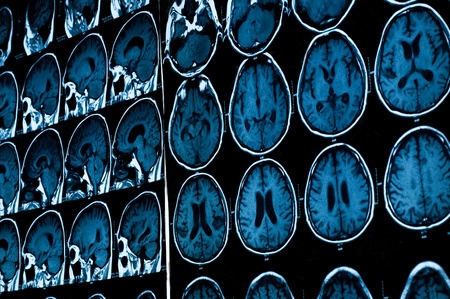

I have been optimistic about the potential for voice recognition for many years. In my 2001 book, Net Attitude: What It Is, How to Get It, and Why Your Company Can’t Survive Without It, I discussed the ability to translate languages. Adoption was slow for a decade, but is now accelerating with Amazon Alexa, Apple Siri, Google Now, Microsoft Cortana, and the Skype Translator. Listening to a voice and converting it to meaningful text is one of many forms of artificial intelligence. IBM Research has developed another form of AI called Avicenna. The Avicenna software can read medical images, structured data, and electronic health records. The result is a productivity boost for radiologists.

IBM’s Tanveer Syeda-Mahmood, a researcher at the company’s Almaden research lab near San Jose, California, and chief scientist on the project demonstrated Avicenna’s potential. Syeda-Mahmood fed Avicenna the case of a 28-year-old woman complaining of shortness of breath. The software examined data from the patient’s medical record and read text notes about family history of the patient. Avicenna also “looked” at digital pulmonary angiogram images of the blood vessels around her lungs. After analyzing all of this information, Avicenna suggested pulmonary embolism as the most likely diagnosis. An independent review by a radiologist made the same diagnosis.